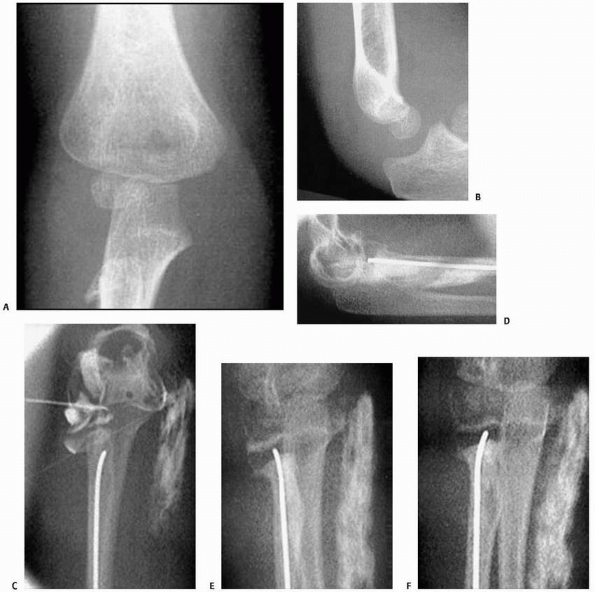

![]() |

FIGURE 11-4 A,B. AP and lateral radiographs demonstrating a radial neck fracture in a patient with a nonossified proximal radial epiphysis. C. Arthrogram prior to reduction demonstrating location/displacement of nonossified proximal radial epiphysis. D-F.

Arthrogram/radiographs after reduction with intramedullary technique. (From Javed A, Guichet J.M. Arthrography for reduction of a fracture of the radial neck in a child with a nonossified radial epiphysis. J Bone Joint Surg Br 2001;83-B:542-543, with permission.) |